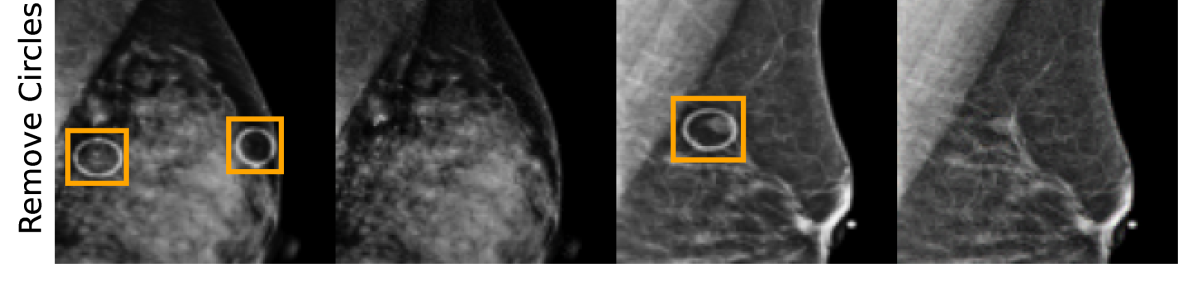

EMBED

Using prior insights, we apply our mechanisms to a real-world artefact removal task on the EMory BrEast imaging Dataset (EMBED) (Jeong et al., 2022). Schueppert et al. (2024) observe that triangular and circular skin markers are spuriously associated with breast cancer in classifiers due to shortcut learning (Geirhos et al., 2020), and manually labelled 22,012 affected mammograms. Using this dataset, we train a significantly scaled-up, amortised, anti-causally guided semantic mechanism () to remove skin markers. We model triangular markers (), circular markers (), breast density (), and cancer () as independent parents of the mammogram , and remove artefacts by intervening on and while holding and fixed. Figure 6 shows that our mechanisms effectively remove artefacts and can disentangle representations for triangles and circles. We successfully remove of triangles and of circles in our test set - a noteworthy result given the dataset’s small size and the scarcity of labelled skin markers (Appendix I).